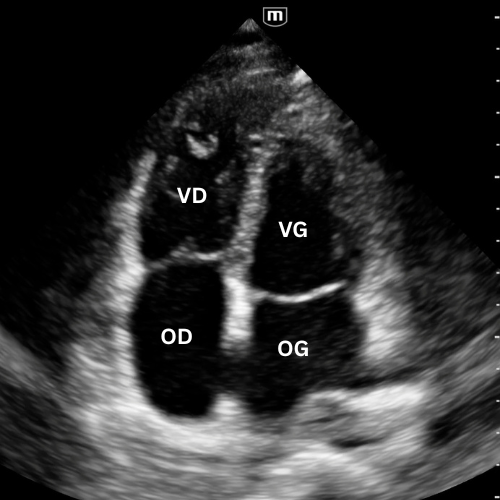

🔹 Vue Apicale Quatre Cavités

→ Quelle cavité domine ?

Placer la sonde près de l’apex (5e espace, région du mamelon gauche), marqueur vers l’épaule gauche. Glisse légèrement jusqu’à un bon espace intercostal, puis bascule la sonde vers la base du cœur jusqu’à voir VG, VD, OG et OD dans le même plan.

On visualise les quatre cavités, les valves mitrale et tricuspide et le septum.

Permet de comparer VD et VG (surcharge droite si VD ≥ VG), d’apprécier la cinétique globale et de repérer un épanchement péricardique circonférentiel.